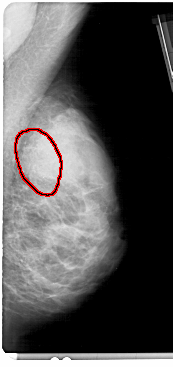

A_1364_1.RIGHT_CC

RIGHT_CC LINES 5041 PIXELS_PER_LINE 2371 BITS_PER_PIXEL 12 RESOLUTION 43.5 OVERLAY

FILE: A_1364_1.RIGHT_CC.OVERLAY

TOTAL_ABNORMALITIES 1

ABNORMALITY 1

LESION_TYPE CALCIFICATION TYPE AMORPHOUS DISTRIBUTION SEGMENTAL

ASSESSMENT 4

SUBTLETY 3

PATHOLOGY BENIGN

TOTAL_OUTLINES 1

BOUNDARY